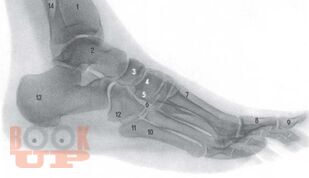

Хирургия диабетической стопы

Монография посвящена хирургическому лечению гнойно-некротических поражений стопы при сахарном диабете. В работе отражен современный взгляд на патогенез, классификацию, клинику, диагностику и дифференциальную диагностику синдрома диабетической стопы. Представлены диагностические и лечебные алгоритмы при гнойно-некротических поражениях стопы для догоспитального и стационарного этапов. Большая часть работы посвящена хирургической тактике и технике наиболее часто производимых хирургических вмешательств на нижней конечности с определением показаний к той или иной операции. Подробно рассматриваются вопросы, касающиеся органосохраняющих вмешательств (локальных операций на стопе). Пособие предназначено практикующим врачам – хирургам, эндокринологам, ортопедам, протезистам поликлиник и стационаров, занимающихся лечением поражений стопы при сахарном диабете.